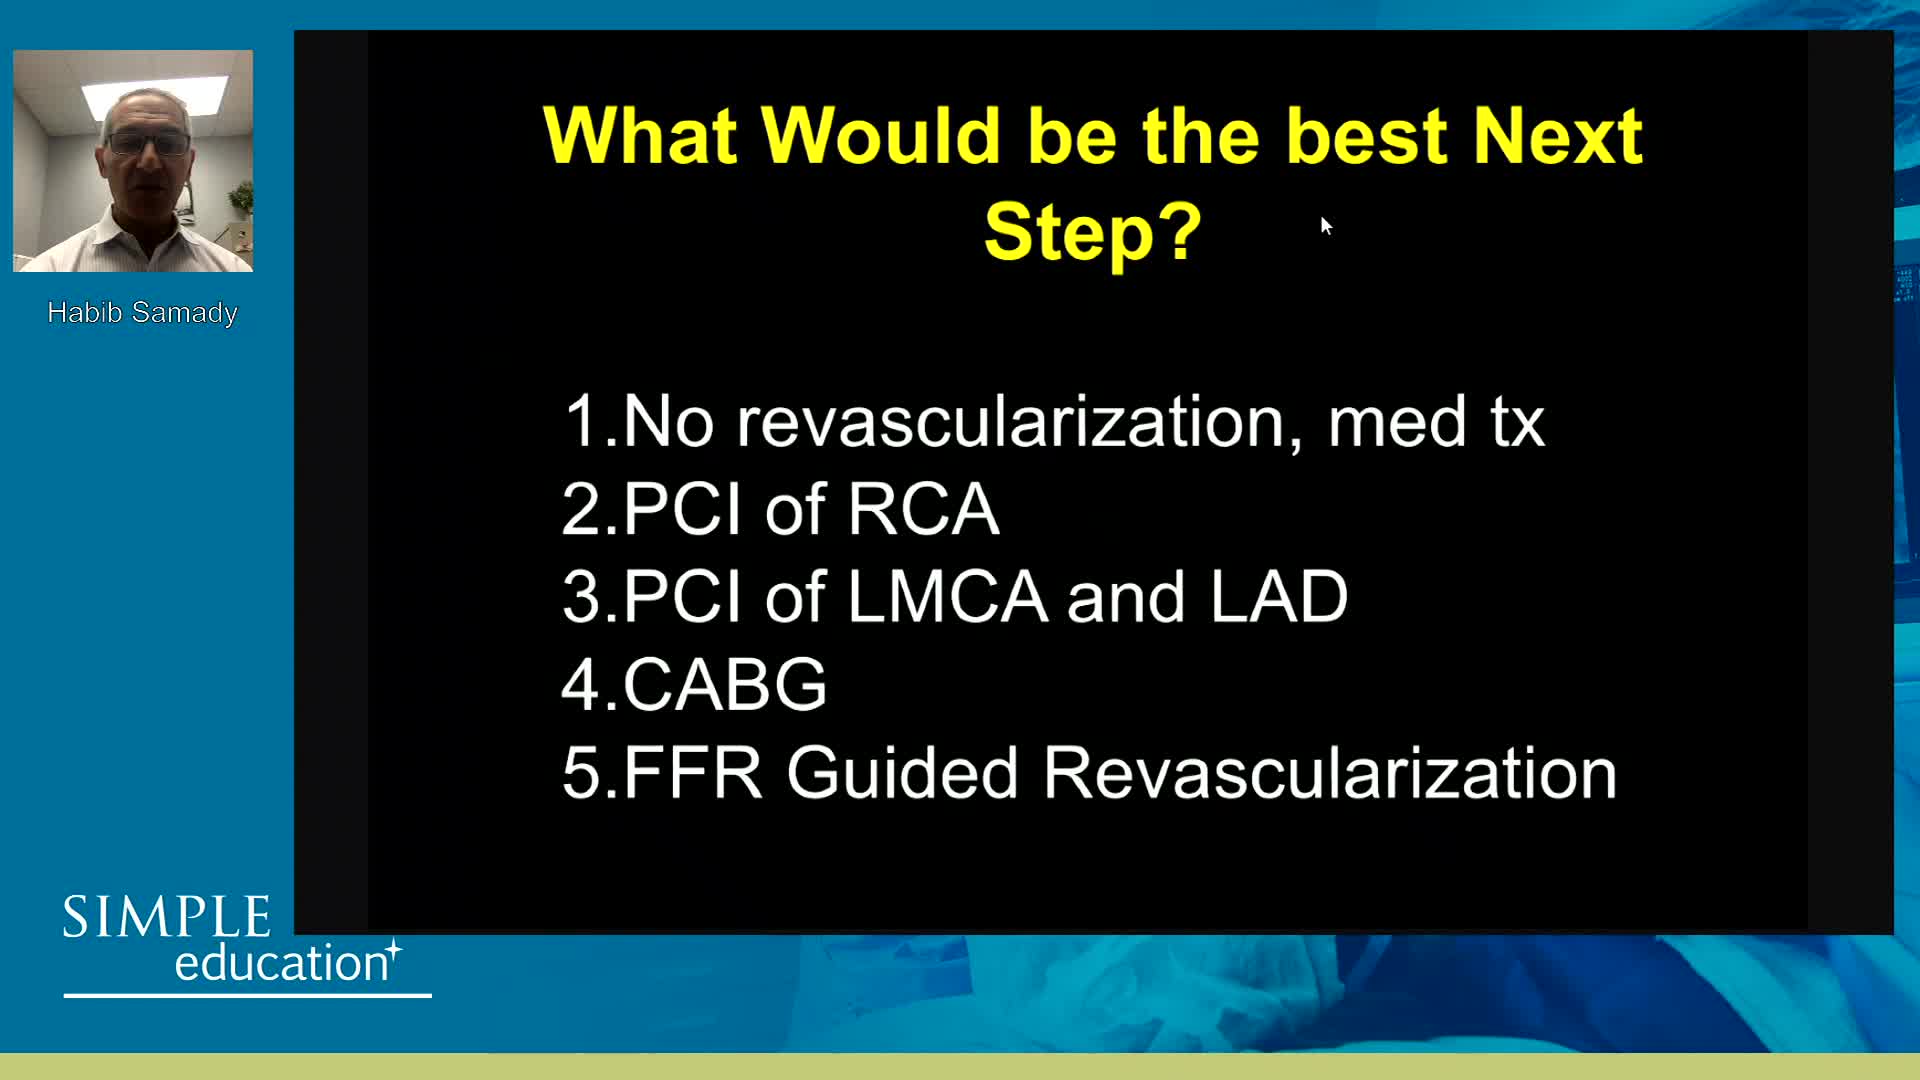

Welcome & Applied coronary physiology to plan and guide PCI-2023 EAPCI Consensus

Can I Measure Coronary Physiology in A.Fib, CHF, Pacing, Cardiogenic Shock, Aortic Stenosis?

Coronary physiology gate keeper or guide to coronary PCI? Rationale and design of DEFINE-GPS

Understanding mechanisms of regulation of resting and hyperaemic blood flow, across single and serial stenoses

20 year overview of clinical trial data to support the use of coronary physiology in revascularisation decision-making